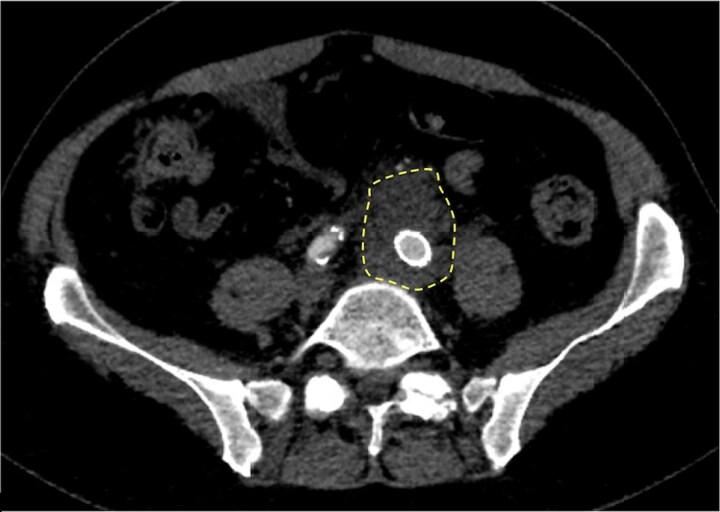

两例因主动脉移植材料感染导致的真菌性动脉瘤

Two Cases of Mycotic Aneurysms Caused by Infection of Aortic Graft Material.

布鲁氏菌作为一种人畜共患病原体,可影响人体多个器官系统,引发各种临床表现。虽然在全球范围内,主动脉髂动脉受累情况较为罕见,但我们报告了在美国佐治亚州一家机构9年内发生的2例腹主动脉瘤修复术后主动脉布鲁氏菌病病例。其中1例为感染性主动脉内移植物,这可能是首次报道。即使在布鲁氏菌病流行地区,主动脉髂动脉感染也很罕见,这凸显了这些病例在佐治亚州的罕见程度。鉴于有症状的主动脉移植物感染预后不佳,我们希望分享成功治疗这些病例的经验,包括感染性主动脉内移植物的治疗经验。我们建议在评估经常接触动物且疑似患有霉菌性动脉瘤的个体时,详细了解病史。必须开展关于防护设备和动物正确处理方法的教育,以降低主动脉移植物布鲁氏菌病感染的风险。我们机构的经验表明,移植物切除和强力霉素 - 利福平是可接受的治疗选择。